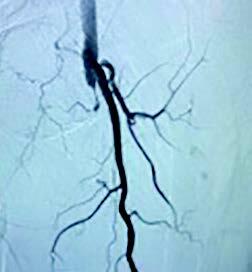

Michael Siah, MD, then took the podium to address the impact of multidisciplinary management of the “no option” patient, sharing several relevant cases. Dr. Siah, an Assistant Professor in the Department of Surgery and the Director of Limb Salvage at the University of Texas Southwestern Medical Center, discussed deep vein arterialization as a potential option under the right circumstances. He added that typically one will need to wait 4-6 weeks following the procedure before undertaking foot surgery to allow for maturation of the pedal venous circuit.5 Early debridement is then limited to removal of infection only, he said, with no closure. He shared additional cases, and concluded by sharing that deep vein arterialization can be safe and feasible for a unique group of patients.